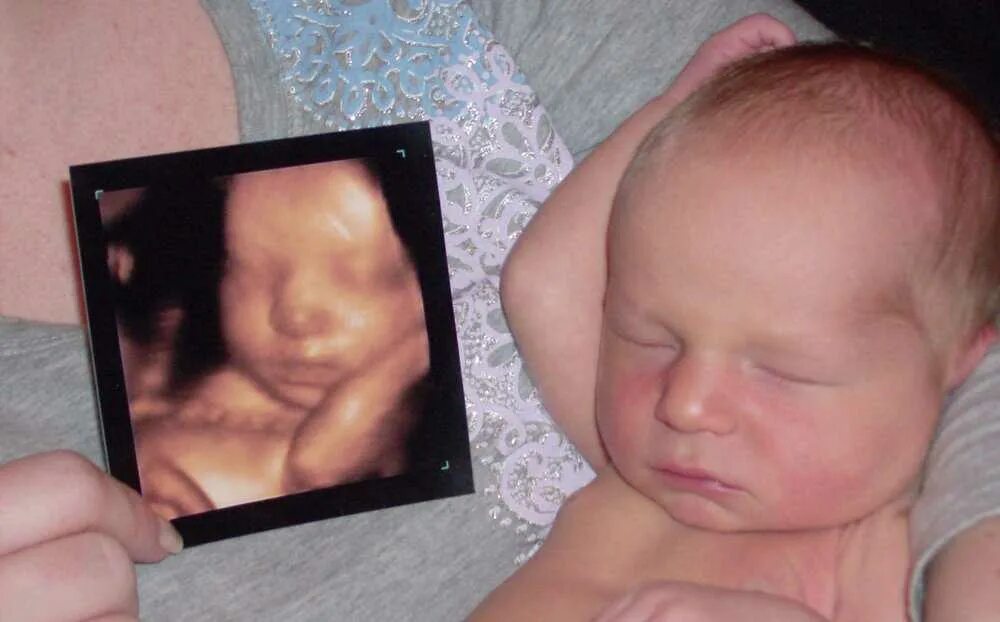

На каком сроке делать 3д